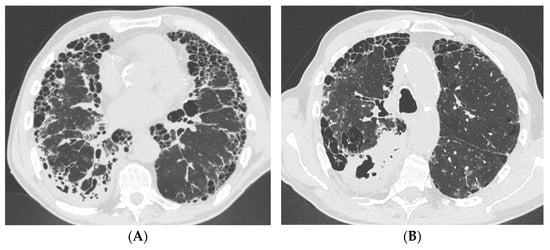

A 82-year-old woman with a history of CTD-ILD secondary to RA and thrombosis of femoral veins was admitted to the Emergency Room for hypoxic–hypercapnic respiratory failure requiring oxygen therapy with FiO2 35% in a febrile state. The patient complained of dyspnea, cough, and weight loss (8 kg) over the previous 3 months. In anamnesis, there was recent close contact with active TB. Laboratory tests revealed elevated inflammatory markers, neutrophilic leukocytosis, moderate anemia, and high D-dimer levels. Chest X-ray showed bilateral reticular diffuse interstitial lung alterations with consolidation in the left upper field. Chest HRCT demonstrated multiple bilateral excavated lesions, parenchymal consolidation with air bronchogram, and a UIP pattern characterized by traction bronchiectasis and reticulation (Figure 2). The patient underwent bronchoscopy with BAL: fluid molecular essay would later result positive for Mtb. Moreover, the mycobacteria growth indicator tube tested positive for TB resistant to isoniazid, rifampin, streptomycin, and pyrazinamide. Therefore, antibiotic therapy with amikacin, amoxicillin/clavulanate, meropenem, clofazimin, cicloserin, bedaquilin, and moxifloxacin was started. During the prolonged hospitalization, the patient received a red blood cell transfusion (two units) for drug-induced anemia. After two months of prescribed antibiotic therapy, a follow-up contrast chest computed tomography (CT) showed the reduction in extension of the excavated lesions and the consolidations and highlighted subsegmental pulmonary embolism. After a cardiological consultation, the patient was finally discharged home with no indication for anticoagulant treatment and no need for oxygen therapy at rest, while maintaining the indication for supplemental oxygen during exertion. The patient died at home the following month, prior to the next scheduled outpatient visit.

Figure 2. Case #2 chest HRCT scans acquired in the emergency room. Multiple bilateral excavated lesions and parenchymal consolidation with air bronchogram are more evident in the upper lobes (A), while the UIP pattern characterized by traction bronchiectasis and reticulation is more prominent in the lower lobes (B). Abbreviations: HRCT, high-resolution computed tomography; UIP, usual interstitial pneumonia.